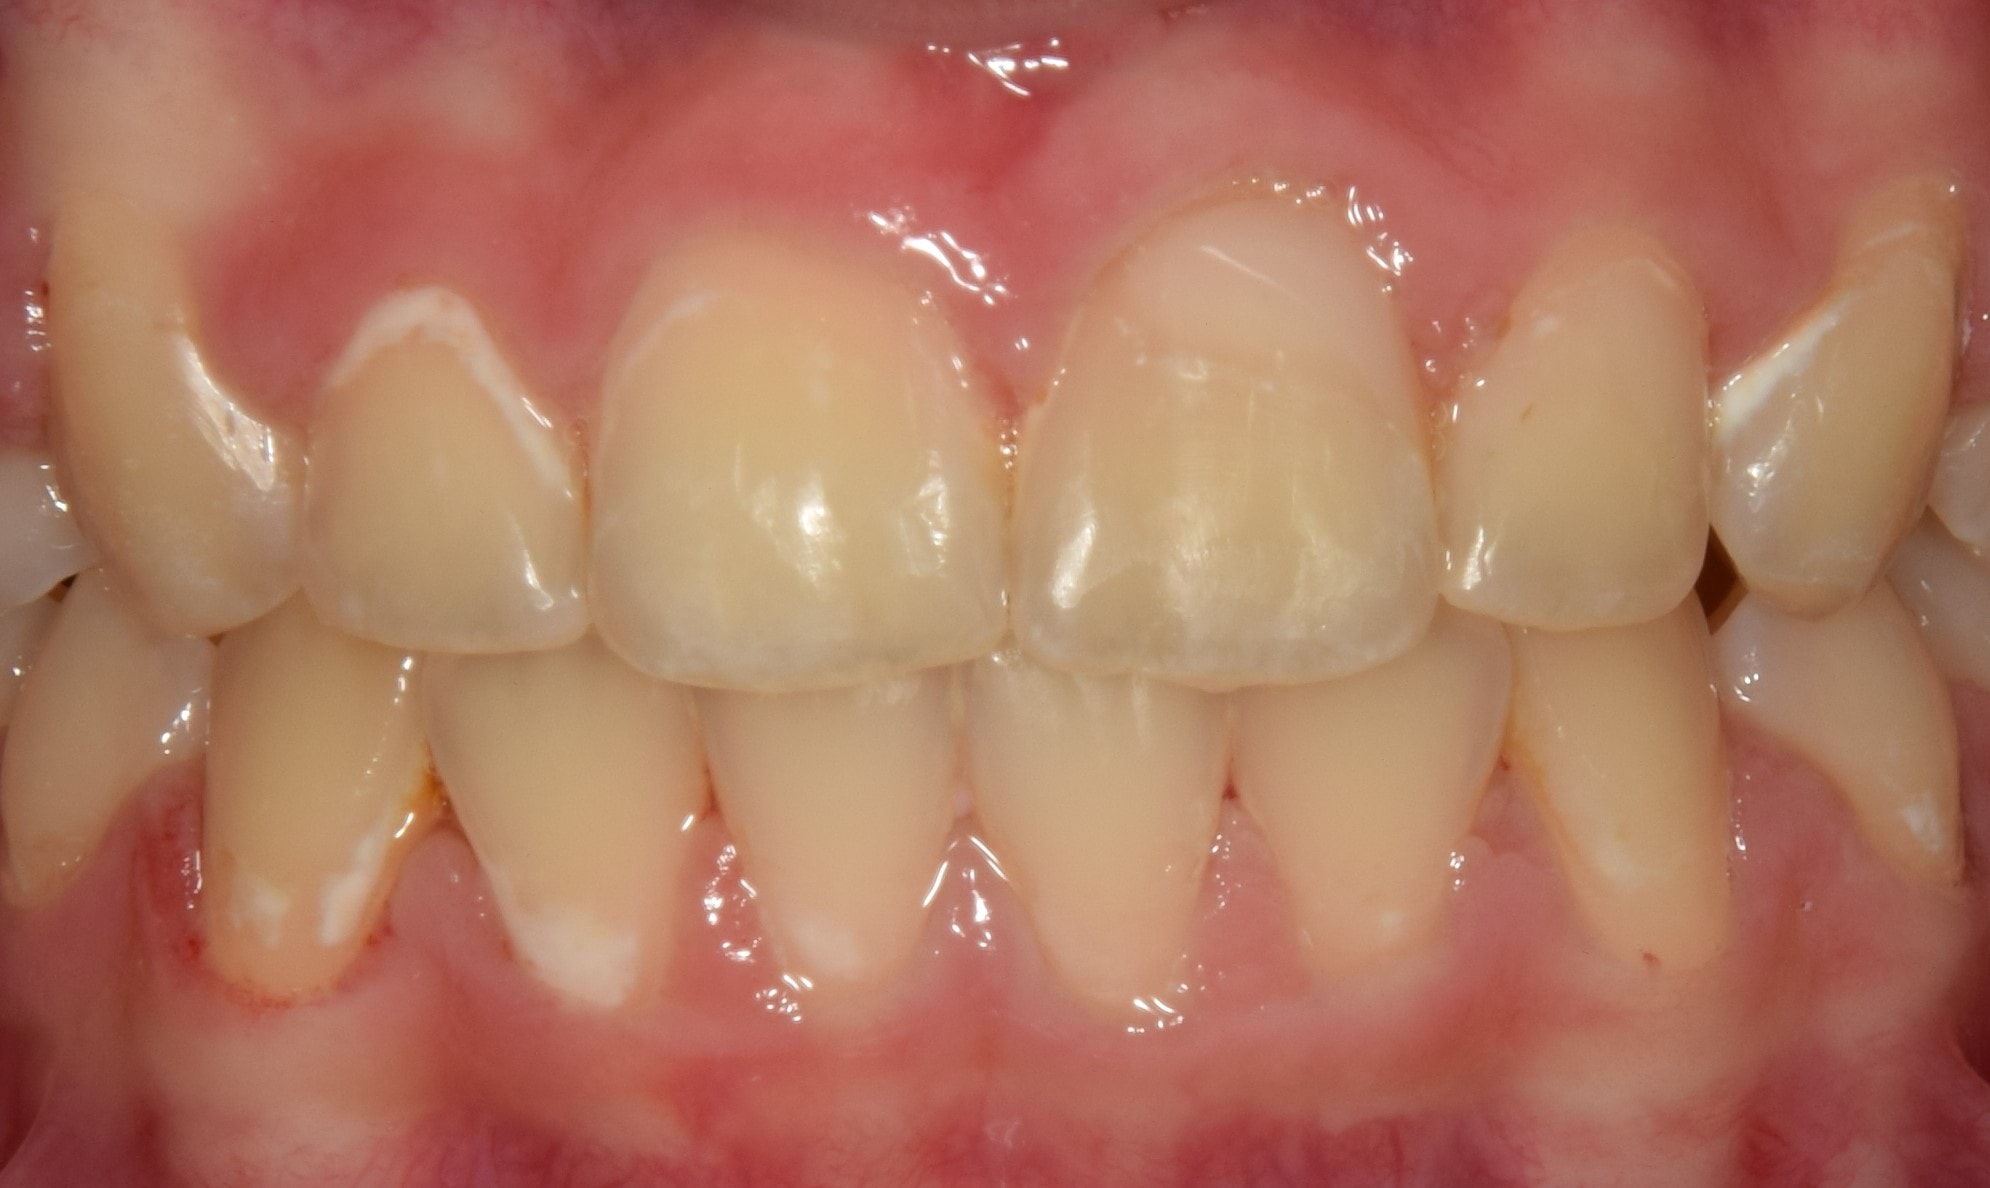

Élpótlás

A felső metszőfogak éli részének esztétikai korrekciója. Készülhet csiszolás nélkül, közvetlenül a fogorvos által, ilyenkor a magas minőségű tömőanyagok segítségével a saját fogtól megkülönböztethetetlen tömés készíthető. Kisebb eltéréseknél javasolt eljárás. Nagyobb egyenetlenségek korrigálására a fog minimális csiszolásával járó héjak készítése a megfelelő választás, amiket fogtechnikus készít el precíziós lenyomat alapján. Ezek általában kerámiából készülnek, szintén hihetetlen pontossággal és esztétikával. Manapság már lehetőség van a kívánt végeredmény vizualizálására mosolytervező szoftver segítségével, sőt, a mosolytervező szoftverbe integrálható egy intraorális scannerel vett lenyomat is, amire a fogtechnikus közvetlenül tudja elkészíteni az élethű héjpótlásokat! A technika ezen a téren a végtelenbe és tovább fejlődik!